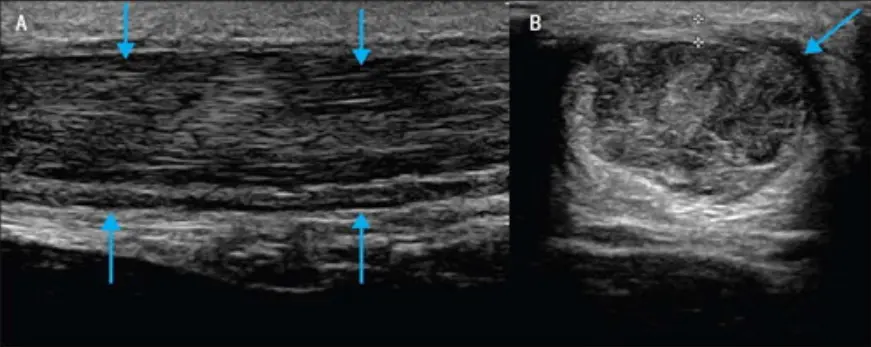

Musculoskeletal Ultrasound

Ultrasound allows us to see:

- Tendon thickening

- Micro-tears

- Degeneration

- Calcifications

- Neovascularization

This helps us distinguish active inflammation from structural breakdown.